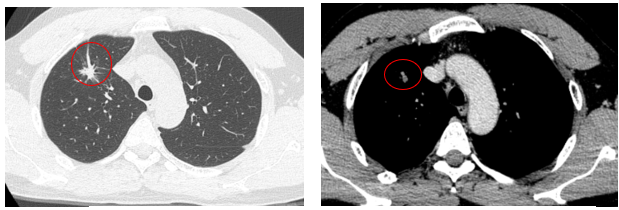

Xử trí: Bệnh nhân được hội chẩn hội đồng chuyên môn, đồng ý chuyển sang điều trị phác đồ ABCP (Bevacizumab – Atezolizumab – Paclitaxel – Carboplatin) từ tháng 07/2024

Đánh giá điều trị phác đồ ABCP sau 3 tháng: Các triệu chứng lâm sàng được cải thiện, bệnh nhân ổn định, không ho, không sốt, không đau ngực, không sờ thấy hạch thượng đòn

Cắt lớp vi tính ngực: Nhu mô thùy trên phổi phải có nốt tổn thương tỷ trọng tổ chức, kích thước ~ 8x11mm, bờ tua gai, cắt cụt nhánh phế quản phân thùy S3m, giãn phế quản lân cận. Ngoài ra nhu mô thùy trên có vài nốt đặc nhỏ <4mm, giới hạn rõ, bờ đều.

Hình 3: Hình ảnh chup cắt lớp vi tính ngực thấy khối u thùy trên phổi phải giảm kích thướcc còn 11x08 mm, bờ tua gai

Đánh giá điều trị phác đồ ABCP sau 6 tháng: Các triệu chứng lâm sàng được cải thiện, bệnh nhân ổn định, không ho, không sốt, không đau ngực, không sờ thấy hạch thượng đòn

Cắt lớp vi tính ngực: Nhu mô thùy trên phổi phải có nốt đặc bờ không đều kích thước 6x4mm, xung quanh có các ổ giãn phế nang và các dải xơ co kéo nhẹ nhu mô phổi, hạn chế đánh giá tính chất ngấm thuốc do kích thước nhỏ. Ngoài ra nhu mô thùy trên có vài nốt đặc nhỏ <4mm, giới hạn rõ, bờ đều. Không thấy giãn phế quản - phế nang.

Siêu âm hạch vùng cổ: Không phát hiện hạch bất thường.